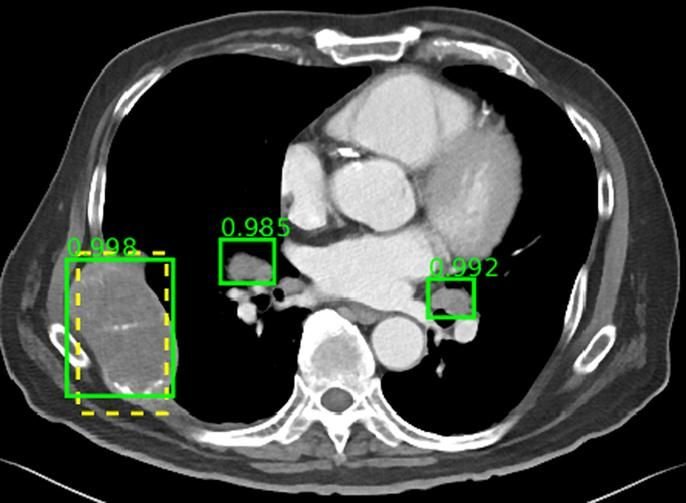

Prevalencia y resultados de hallazgos de imágenes incidentales (inesperadas)

BMJ, 18 de junio de 2018 Existe una gran variabilidad entre las diferentes técnicas de imagen tanto en la prevalencia de incidentalomas como en la prevalencia de malignidad de órganos específicos. Esta revisión general ayuda a los médicos y pacientes a sopesar los pros y los contras de solicitar escaneos de imágenes y ayuda con las decisiones de manejo después de un diagnóstico de incidentaloma. Nuestros resultados pueden respaldar la creación de pautas para ayudar en estas decisiones.